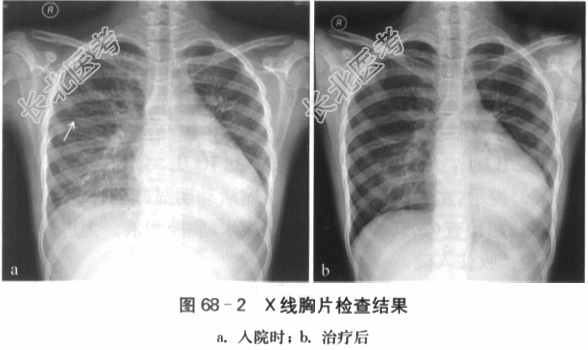

(2)胸部X线检查:胸廓对称,气管居中。两侧透亮度正常,肺纹理显著,未见明显渗出影,双侧中下肺野外带见克氏B线,水平裂增厚,右侧胸膜影稍增宽。肺门影增浓,肺门角欠清晰。心影明显增大,心尖向左下延伸,心胸比例0.60。左膈面显示不清,右膈面光整,右侧肋膈角锐利。结论:心影增大,间质性肺水肿(见图68-2-a)。治疗1周后,心影仍大,间质性肺水肿好转(见图68-2-b)。